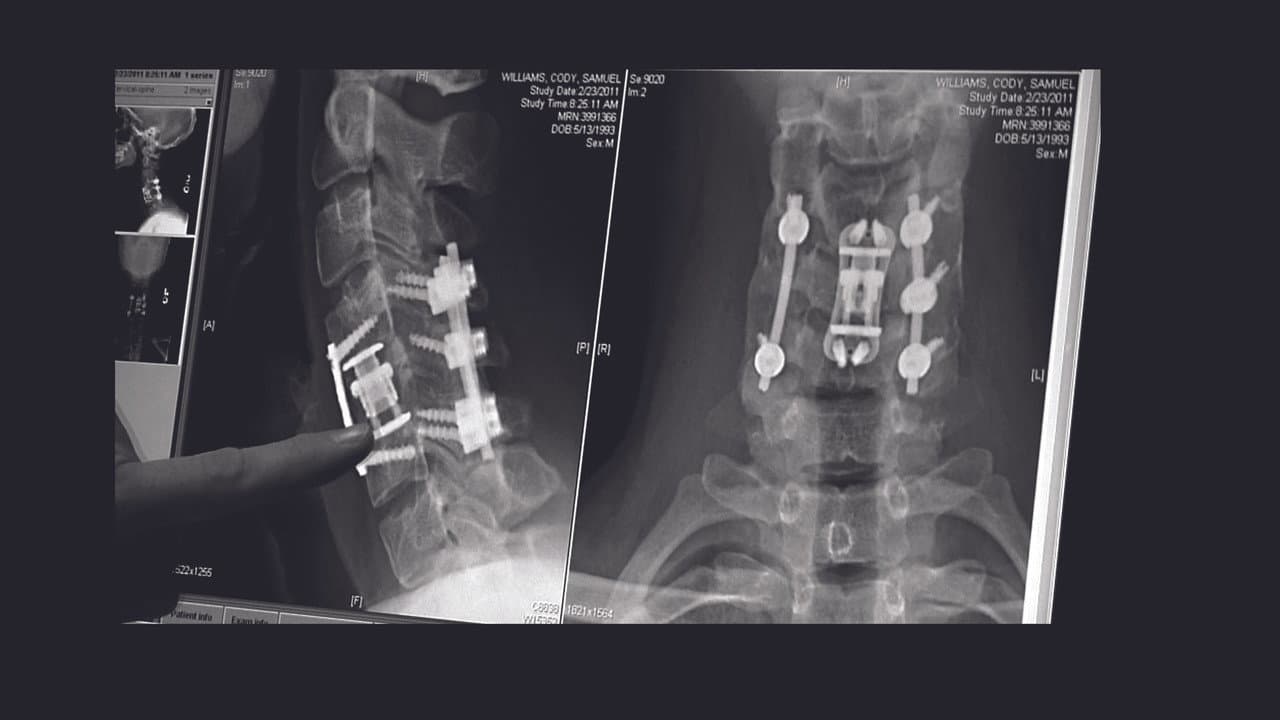

The compelling, heart-wrenching story of high school football star Chris Carnales, whose life changed when he became paralyzed after breaking his neck in a football game. Chris soon learned of others who suffered similar injuries and, with the help of his father, overcame tremendous pain to start an organization with one goal in mind: get immediate help to other victims and their families. He called it Gridiron Heroes.